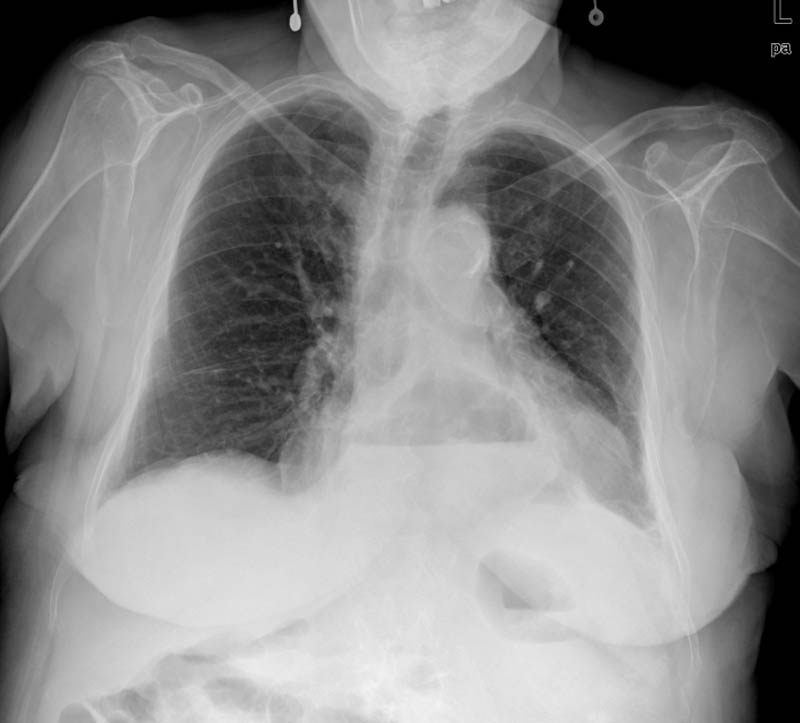

Fibrosis pulmonar. ICC.